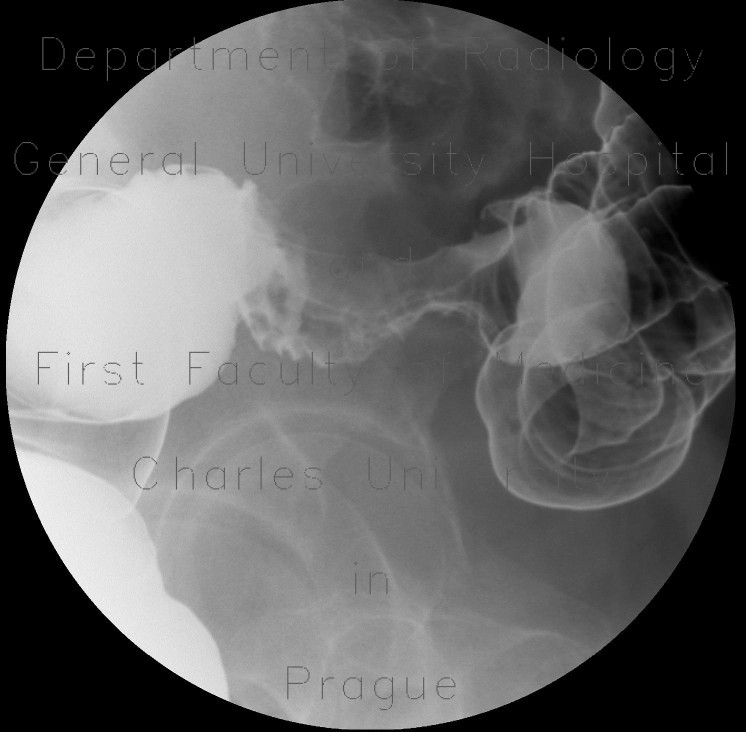

Case Report: Solitary Ischaemic Small bowel stenosis

Case report: Solitary ischaemic small bowel stenosis stenosis in the patient presented here and was confirmed by histological examination. In conclusion, the present case illustrates the need to ... Retrieve Document